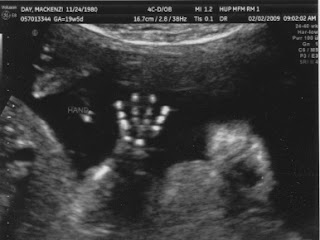

And here's how baby is progressing this week...